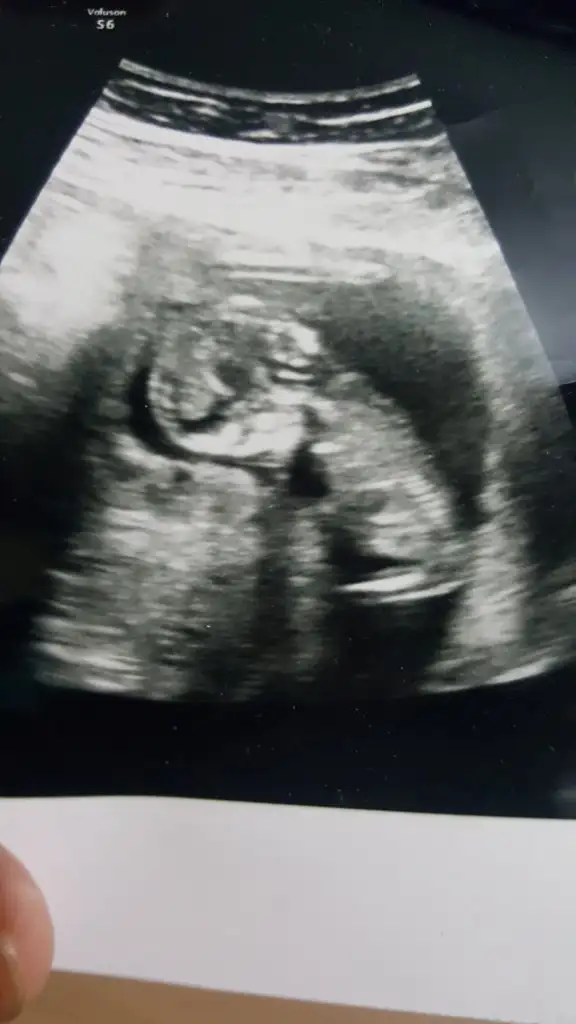

Bende yeniyim öncelikle☺️Mesajlarınızı dikkatle okudum bana da doktorum kesin birşey demedi 13.haftadayım yorumlar Mısınız acaba

Merhabalar bizimde bebeğimiz 12 haftalarda yorumlarsanız çok sevinirim Ikra meyra Ikra meyra